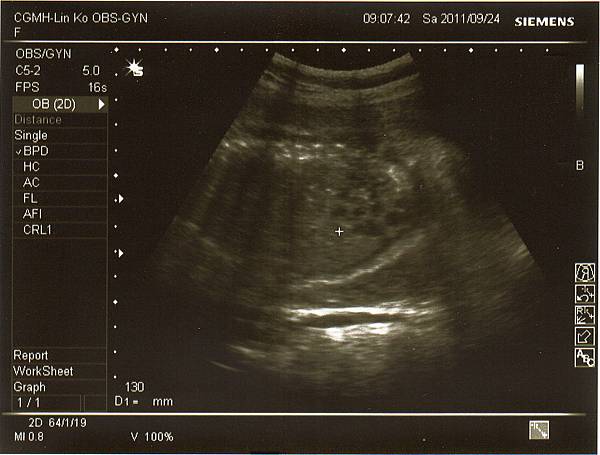

醫生說很重要的兩條動脈~

兔妹妹的腎臟(不過我實在看不太懂)~